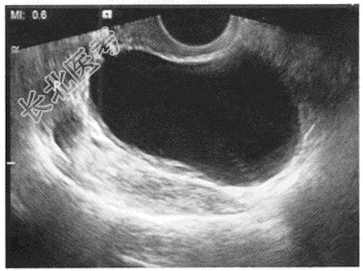

- 单项选择题女,25岁, B超检查如图所示,最可能的诊断为

A、右卵巢癌

B、右侧输卵管积液

C、右卵巢卵泡

D、右卵巢囊肿

E、扩张的右侧输尿管